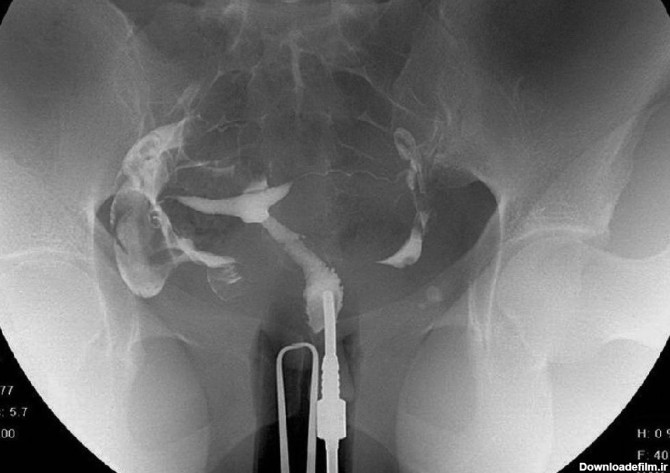

عکس رنگی رحم با یک لوله

عکس رنگی رحم با بیهوشی یا بدون درد یکی از خواسته های بانوان است که از حدود شانزده سال پیش توسط دکتر مقدس زاده در مرکز پرتو طب آزما قم در حال انجام است.